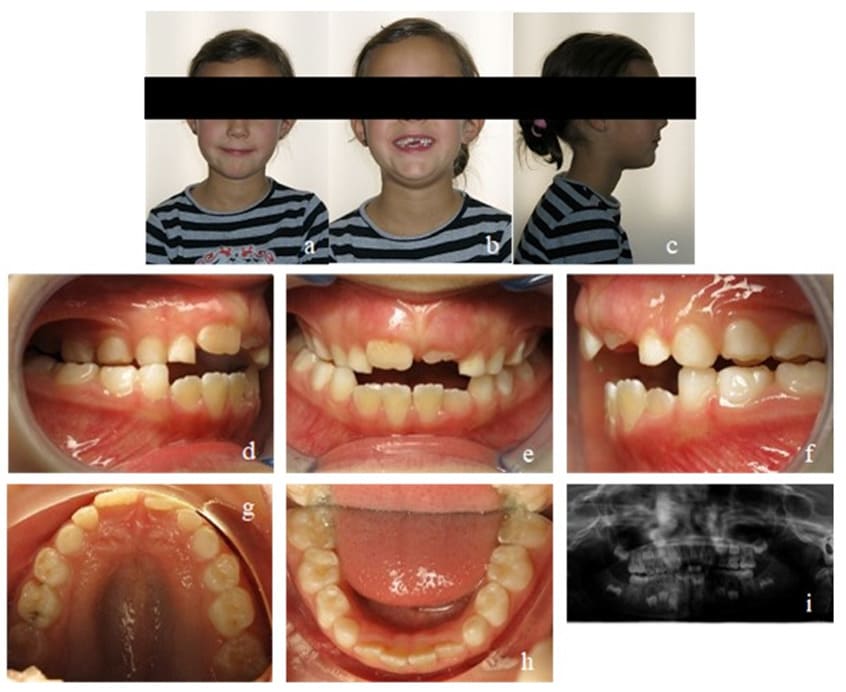

This patient was transferred to our orthodontic office by her speech-therapist at the age of 6. During initial diagnosis, a unilateral posterior cross bite on the right side and an anterior open bite of 3 mm were apparent. Accordingly, the upper arch was too narrow and needed further transversal development. Mild crowding in the lower front segment and an exaggerated Wilson’s curve of the lower permanent and deciduous molars could be seen. The dental situation confirmed the myofunctional diagnosis of a habitual open mouth posture, infantile swallowing, a low resting position of the tongue and enlarged palatine tonsils. Nasal polyps had already been removed at an earlier stage (Figure 10).

Figure 10: Case 2. Initial findings. En face (a, b) and profile of the patient (c). Frontal view of the occlusion (e), occlusion right (d) and left (f). Upper (g) and lower arch (h). Initial Panoramic x-ray (i).

Our initial orthodontic goal was the posterior cross bite elimination by maxillary expansion to create enough space for the tongue. The second goal was to straighten up the lower molars and to close the anterior open bite. Myofunctional goals comprised the establishment of nasal breathing, mature swallowing, and the physiological resting position of the tongue.

The most important task during the first treatment phase was to expand the maxilla. Due to their comparatively soft structure, parttime worn EGAs alone are not suitable to perform that expansion. Therefore, in addition to an appropriate EGA, the patient received a removable appliance named Bioplate (Figure 1) based on the Biobloc invented by Mew (orthotropics). It is worn for 24 hours per day and is only removed once a day for cleaning and daily activation. Maxillary incisor protrusion, maxillary expansion as well as a lateral bite block in combination with provision of improved space for the tongue on the anterior palate are the major advantage of this appliance. Additionally, the Bioplate is almost invisible, allows clear speaking, and can be worn in combination with an EGA to straighten up the lower molars, aligning the lower teeth, allow bite jumping and influence mouth breathing as well as tongue posture.

After the first treatment phase, the posterior cross bite was corrected and the anterior open bite reduced, but still remained present. The patient adapted the mature swallowing pattern rather quickly, but an interdental lisp remained and showed extensive tongue movement while wearing the EGA. The strength of the tongue was still low (Figure 11). The appliance of choice for the second phase was a Bionator instead of an EGA, because a Bionator allows speaking and can therefore be worn for more hours during the day. We controlled compliance with a Theramon® chip (MC Technology GmbH, Hargelsberg, Austria). The tongue movements calmed down and its strength increased while the open bite was further reduced to 1 mm. The maxillary transversal width was successfully retained. Mouth breathing could still be observed at times (Figure 12).